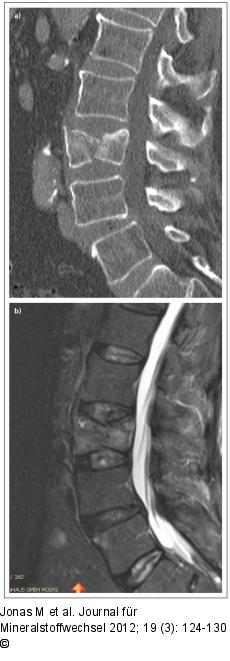

Abbildung 7a-b: Sagittaler Spaltbruch Präoperatives (a) CT und (b) MRT zeigen einen sagittalen Spaltbruch Typ A 2.1 von kranial zu kaudal an LWK III. |

Präoperatives (a) CT und (b) MRT zeigen einen sagittalen Spaltbruch Typ A 2.1 von kranial zu kaudal an LWK III. |